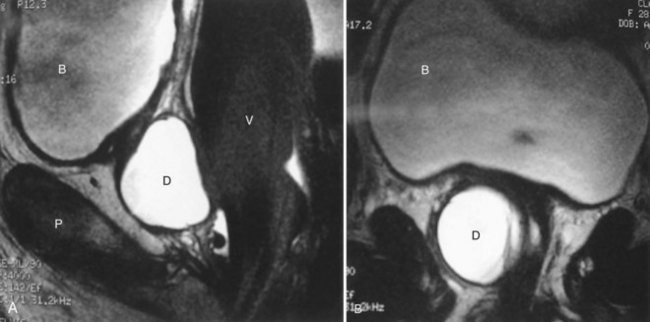

As an alternative to the radiologic investigations noted previously, MRI permits relatively noninvasive, high-resolution, multiplanar imaging of UD. UD appear as areas of decreased signal intensity on T1 compared with the surrounding soft tissues, and have high signal intensity on T2 images. A distinct advantage of MRI compared with VCUG is that successful imaging of UD is wholly independent of voiding and that it is free from ionizing radiation. Surface coil (Hricak et al, 1991; Kim et al, 1993) (Fig. 78–22) and endoluminal techniques (Siegelman et al, 1997; Wang and Wang, 2000; Blander et al, 2001; Lorenzo et al, 2003) have been described. Endoluminal imaging (eMRI) places the magnetic coil into a body cavity adjacent to the area of interest. This location produces an improved signal-to-noise ratio and high-resolution imaging of these areas (Siegelman et al, 1997; Blander et al, 2001). For the evaluation of UD, the coil is placed intravaginally or intrarectally. Both surface coil MRI and eMRI appear to be superior to VCUG and/or PPU in the evaluation of UD (Kim et al, 1993; Neitlich et al, 1998; Blander et al, 2001), but the technology is expensive and not widely available. Contraindications to MRI for UD are few; these include metallic foreign body fragments, claustrophobia, and an inability to tolerate the endoluminal probe.

Figure 78–21 Voiding cystourethrogram (VCUG) and MRI from a patient with a large circumferential urethral diverticulum (UD). The voiding image from the VCUG (A) shows poor opacification of the proximal urethra with suboptimal distention of the UD due to a poor voiding effort. The endoluminal MRI demonstrates the full extent and complexity of the lesion on the T2 axial (B), midline sagittal (C), and parasagittal (D) images.